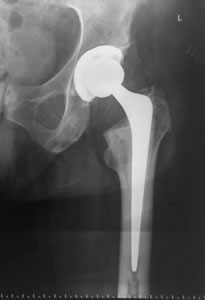

• Reemplazo articular con prótesis

La sustitución protésica permite la carga inmediata para devolver a los pacientes ancianos a la actividad y ayuda a evitar las complicaciones del encamamiento y la inactividad.